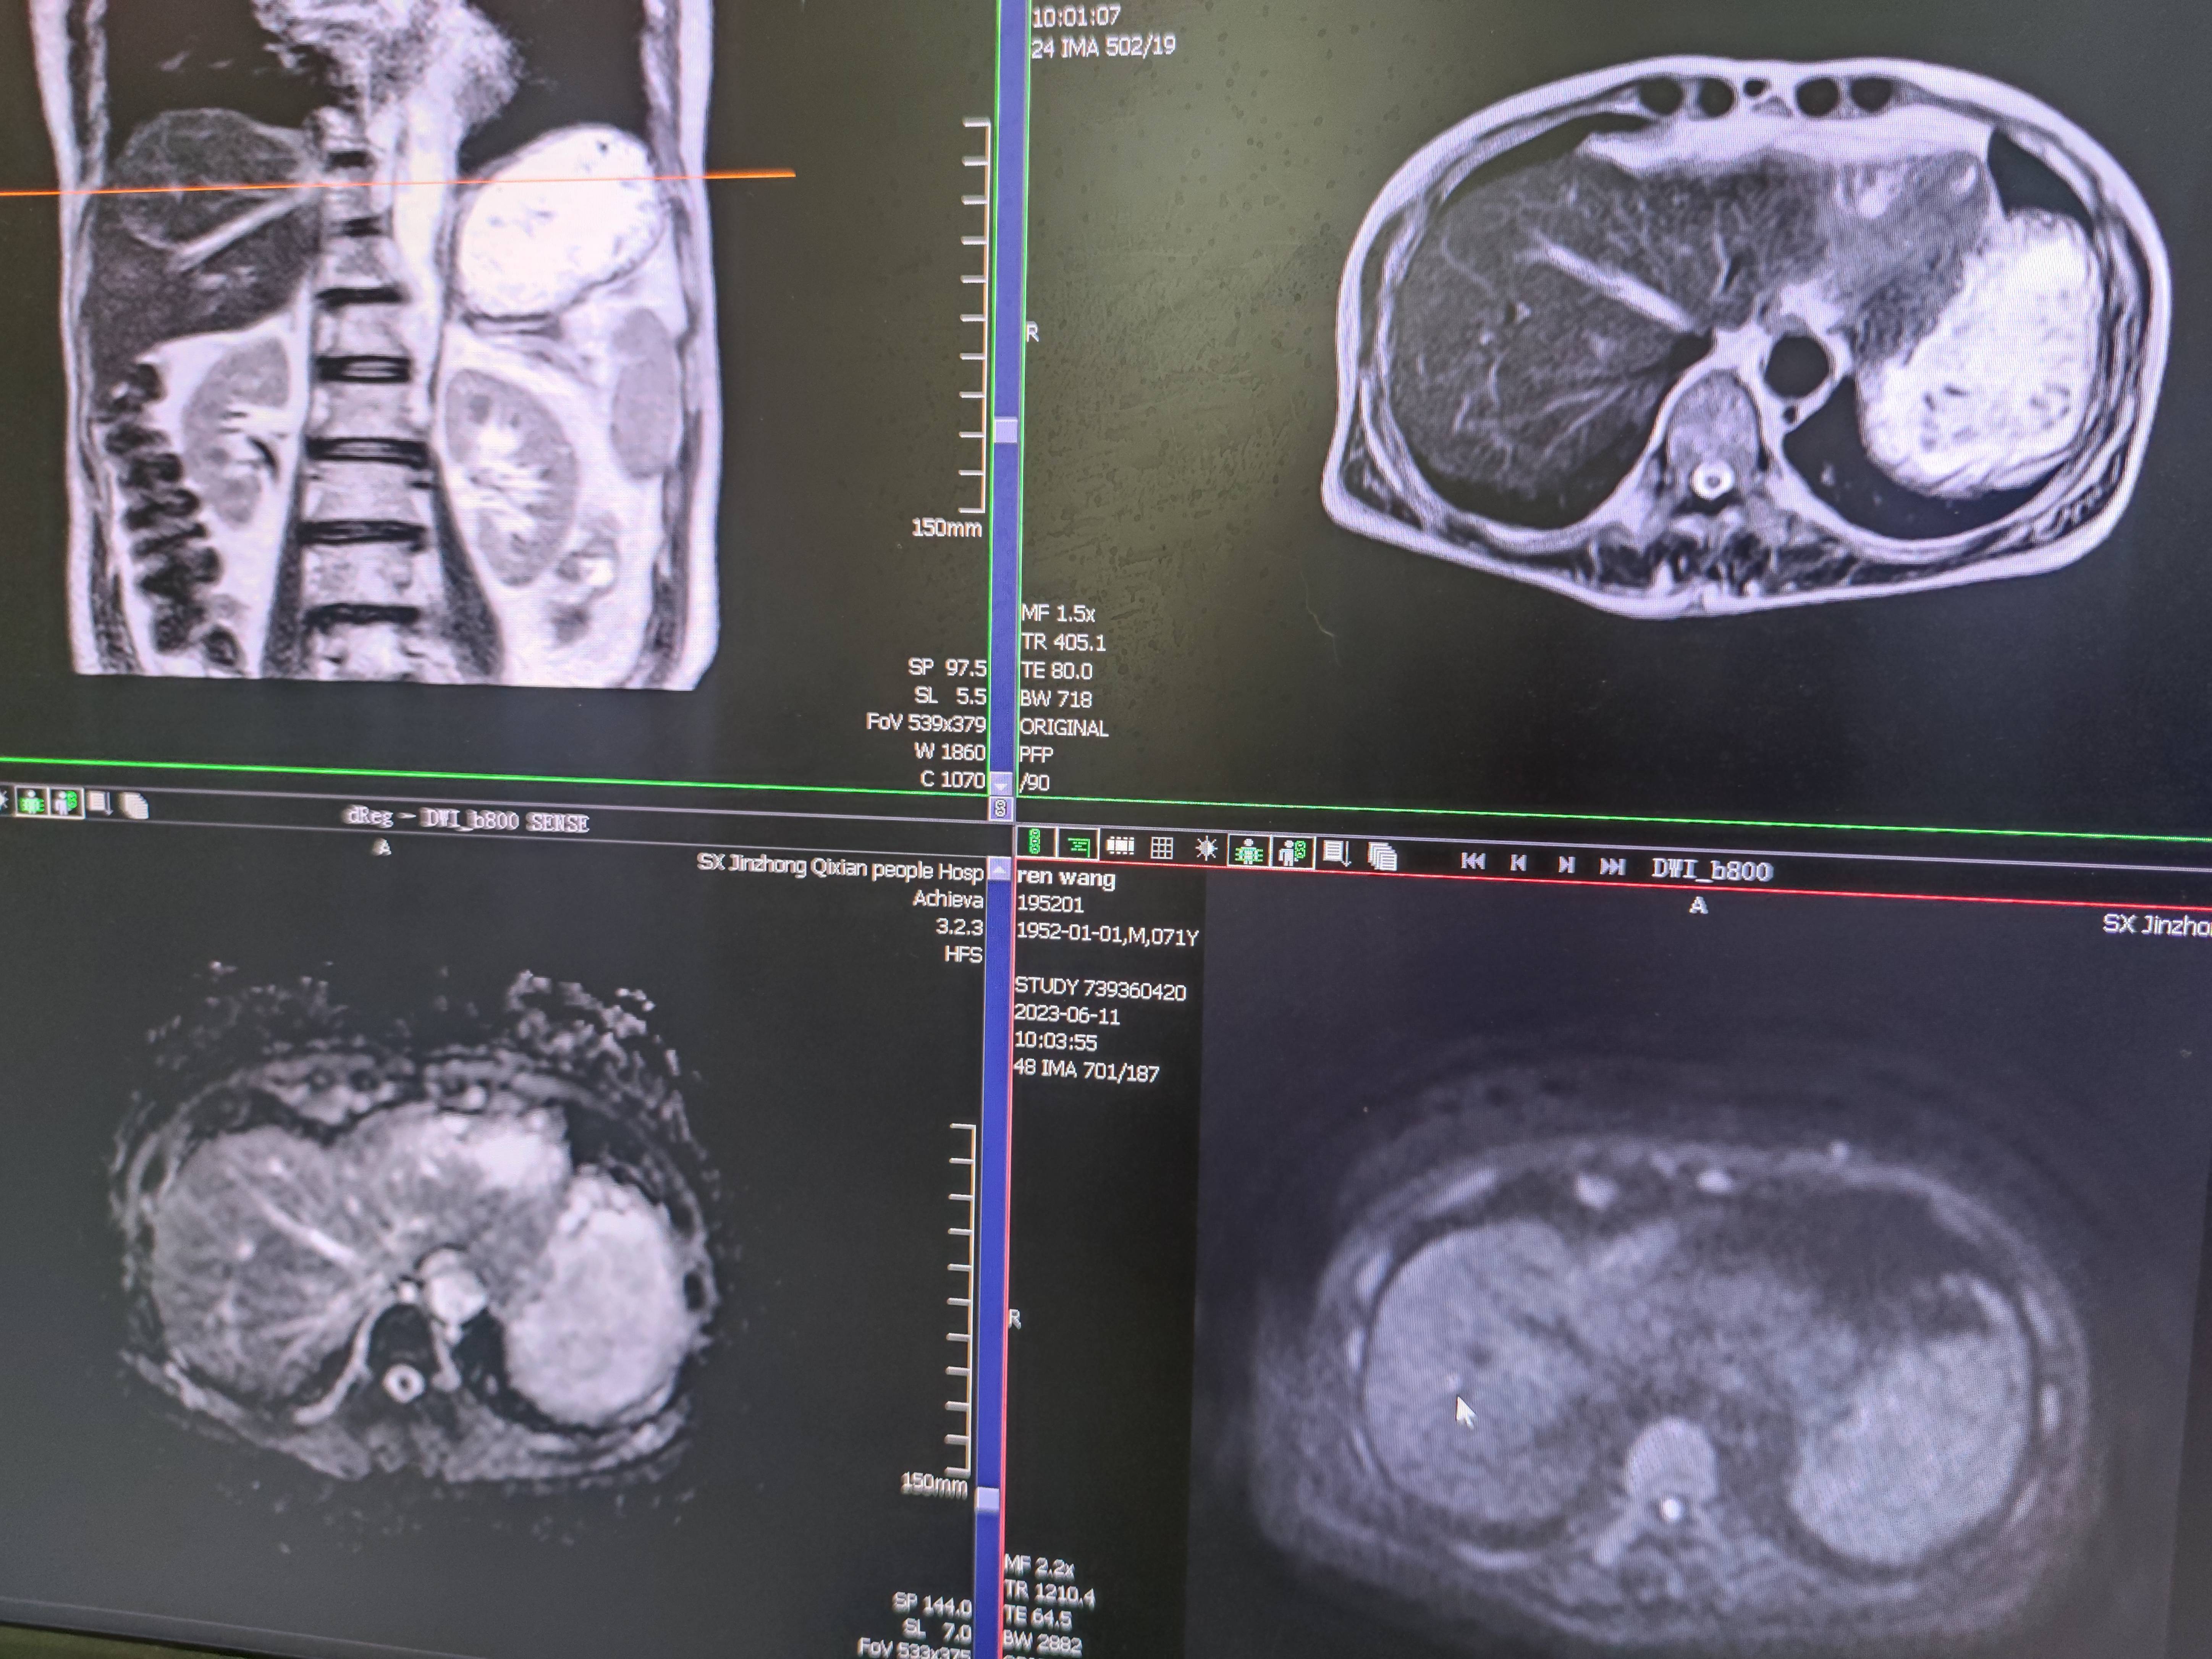

四月份癌胚抗原还是5.6,这个月到8了,持续升高。做了核磁增强,左侧桥小脑角哪有个地方不确定。肝脏核磁平扫弥散有两个点状高信号,转移也排不了,胃肠镜正常,左颈部有个变圆的淋巴结,保险点是不该加个化疗药了?咨询了陈波主任,等结果的吧!图片